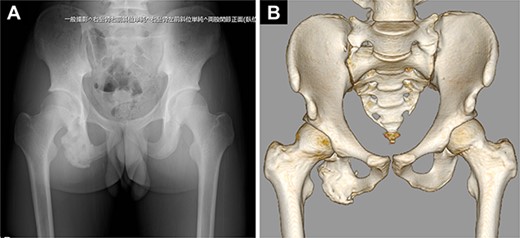

Pelvic images revealed the avulsion fracture of the right ischial tuberosity with severe displacement of the avulsed fragment (Fig. 1A–D). We performed ORIF 5 days after the injury. The patient was placed in the prone position under general anesthesia with the hip and knee joints in slight flexion (Fig. 2A). A 10-cm longitudinal skin incision was made 1 cm lateral to the ischial tuberosity and the subgluteal approach was performed (Fig. 2B). The avulsed fragment was displaced in the distal direction (Fig. 3A) and repositioned by posterior extension of the hip and flexion of the knee joint.

Preoperative images of the pelvis. (A) Pelvic radiograph showing the displaced avulsion fracture of the ischial tuberosity (white arrow). (B, C) Computed tomography scans show the displaced avulsed fragment. The avulsed fragment was displaced by 35 mm. (D) The size of the avulsed fragment was 55 × 17 mm.